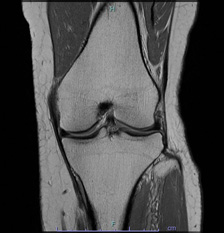

• 画像:損傷後内側半月板MRI画像(側面)

損傷後内側半月板MRI画像(側面)

• 画像:損傷後内側半月板MRI画像(正面)

損傷後内側半月板MRI画像(正面)